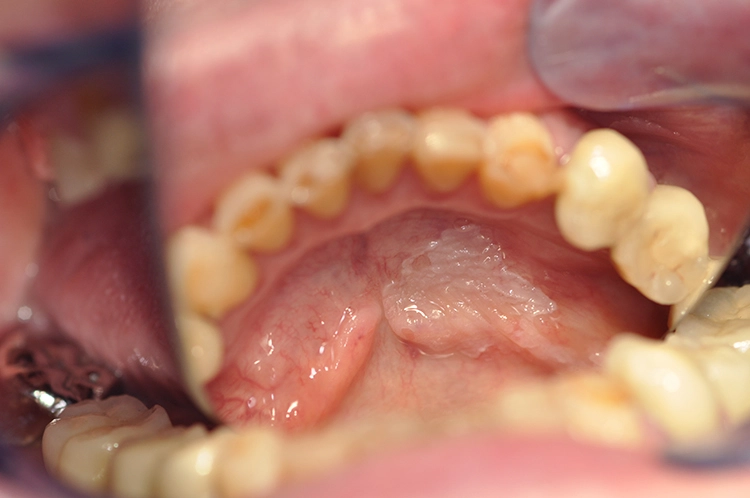

Veränderungen der Mundschleimhaut können vielfältig in Erscheinung treten. Häufig sind es entzündliche Stomatitiden, die sich einfach mit prednisolonhaltiger Salbe behandeln lassen (z.B. Dontisolon®) [2]. Leukoplakien lassen sich dagegen schwerer genau bestimmen. Sie zeigen sich als vornehmlich weiße Läsionen, die weder klinisch noch histologisch einer anderen Mundschleimhautveränderung zugeordnet werden können [3].

Tritt innerhalb von 2 Wochen keine Besserung bzw. Ausheilung der Mundschleimhautveränderung ein, besteht der Verdacht einer Vorläuferläsion, die von einem Spezialisten histologisch auf ihre Dignität hin untersucht werden muss [1,4].